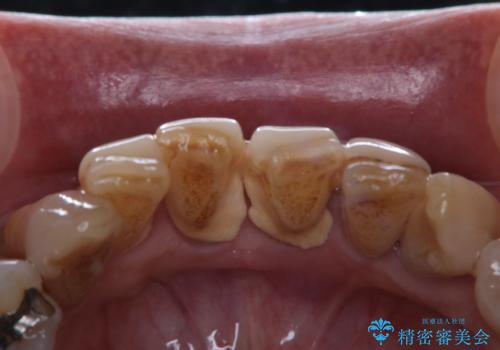

プラークが放置されると、そこで病原菌が繁殖し始めます。そうなるとバイオフィルム(歯面に強固に付着したばい菌の膜)になり、歯肉に炎症が生じ歯周病の引き金となります。

プラークやバイオフィルムといった細菌などを放置すると歯石となります。歯石になってしまうと歯磨きでは取り除くことができないため、歯科医院にて専門的な機械や材料を使用してクリーニングを受ける必要があります。

PMTCは審美的な面だけではなく、虫歯や歯周病予防にもなります。虫歯や歯周病予防のためには、お口の中を清潔に保つことが大切です。